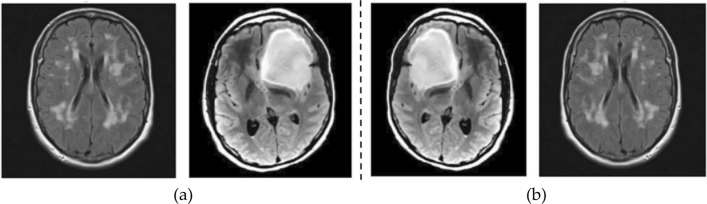

This augmentation strategy contributes to a more comprehensive and diverse training dataset, empowering the model to generalize better across a myriad of scenarios. The utilization of ImageDataGenerator during model training yields a twofold advantage. Firstly, it ensures that the deep learning model is exposed to a richer set of training examples, facilitating improved learning of intricate patterns and features. Secondly, the automatic generation of augmented images enhances the model's robustness by making it less susceptible to overfitting and more adaptable to diverse input variations. This augmentation-driven approach has been recognized for its efficacy in enhancing the overall performance of deep learning models, leading to improved accuracy and resilience in real-world applications35. Figure 3 depicts the normal and augmented images of brain MRI.

Figure 3.

Augmentation (a) normal; (b) augmented images.